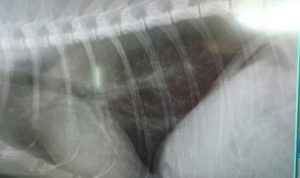

このデカ忌々しいやつがない!↓

ほうら!